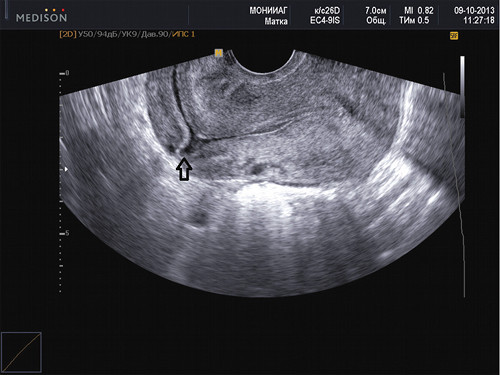

Методы диагностики

Ультразвуковое исследование (УЗИ) является ключевым методом для диагностики рубцовой недостаточности. В процессе проведения данного обследования специалист обращает внимание на следующие аспекты:

- общее состояние операционного шва;

- наличие пустот, вмятин, выпуклостей (лигатур) и мелких разрывов в области шва;

- толщину рубцовой ткани;

- возможные патологические изменения слизистой оболочки в месте наложения шва.